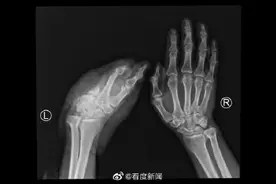

一位来自浙江省温岭市,被机器铰砸致断掌的重伤员在上海顺利接受再植手术,血供重建成功。据悉,工人杨先生(化名),在工厂里干活时,不慎被机器铰砸,导致左手掌不全离断,仅桡侧缘和尺侧缘部分组织相连。当地医院初步诊断为“左手挤压离断伤”。